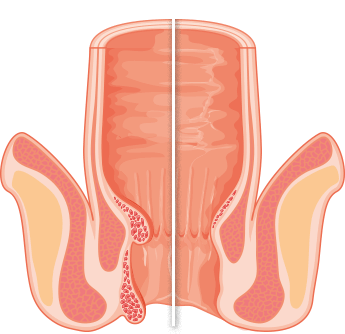

Causas de la aparición de hemorroides

-

Genética

Resultó que el 85% de los parientes consanguíneos también tenían síntomas de hemorroides

-

Estilo de vida sedentario

Esto se aplica principalmente a los conductores y trabajadores de oficina

-

Embarazo

El útero agrandado presiona los vasos del ano, lo que hace que surjan ganglios hemorroidales externos

-

Género

Las mujeres tienen hemorroides por un estilo de vida sedentario y saltos hormonales, y los hombres por cargas excesivas y levantamiento de pesas

-

Factor mecánico

Lesiones, quemaduras y otros efectos mecánicos en el recto y el ano

- Sangrado durante la defecación o presencia de sangre en las heces.

- Desprendimiento de nódulos del recto.

- Sensación de cuerpo extraño, sensación de pesadez.

- Picazón y ardor en el área del ano.

- Dolor al defecar, caminar y estar sentado.

¿qué hace peligrosas las hemorroides en hombres y mujeres?

Inflamación e infección de la mucosa rectal

Inflamación e infección de la mucosa rectal El sangrado puede conducir al desarrollo de anemia

El sangrado puede conducir al desarrollo de anemia El aumento de la temperatura corporal, con inflamación severa, puede provocar fiebre

El aumento de la temperatura corporal, con inflamación severa, puede provocar fiebre ¡Y lo peor es el cáncer rectal!

¡Y lo peor es el cáncer rectal!